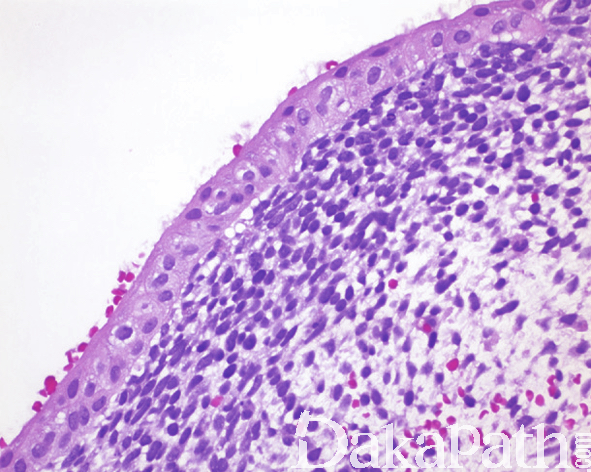

- 肿瘤位于黏膜下,表面黏膜上皮完整,也可增生或有溃疡形成;

- 低倍镜下呈宽乳头状或分叶状;

- 在紧靠黏膜上皮的下方由深染密集的瘤细胞形成一宽带状区域,数层至十数层,称为“形成层”;

- 形成层以下为黏液样区域,间质疏松、黏液水肿样,内有散在的分化程度不一的梭形、卵圆形或圆形横纹肌母细胞,可见核分裂像;

- 当伴有感染时,间质内可见大量的急慢性炎症细胞浸润,有时可掩盖瘤细胞,导致漏诊。